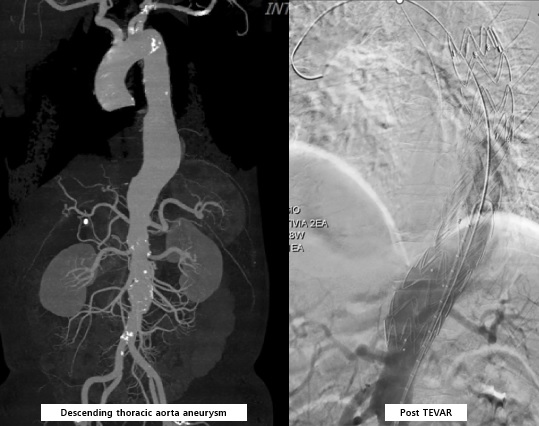

A55-year-old man with previous percutaneous coronary intervention for STEMI, vertebrobasilar infarction, and recent thoracic endovascular aortic repair (TEVAR) for a descending thoracic aortic aneurysm presented to the emergency department with acute chest and back pain without any trauma. He also had hypertension, diabetes, hyperlipidemia, and routinely take the medication. On arrival, his vital signs showed a markedly elevated blood pressure of 178/120 mmHg, while the others within normal limit.

EKG showed no new ischemic changes. Laboratory result revealed mildly elevated inflammatory markers and NT-proBNP, with normal troponin. CT angiography identified a 5.9¡¿6.5 cm giant RCA aneurysm with thrombus, total mid-distal RCA occlusion, a fistula to the right atrium, and also probable acute pulmonary embolism involving the segmental branch of the right lower lobe.